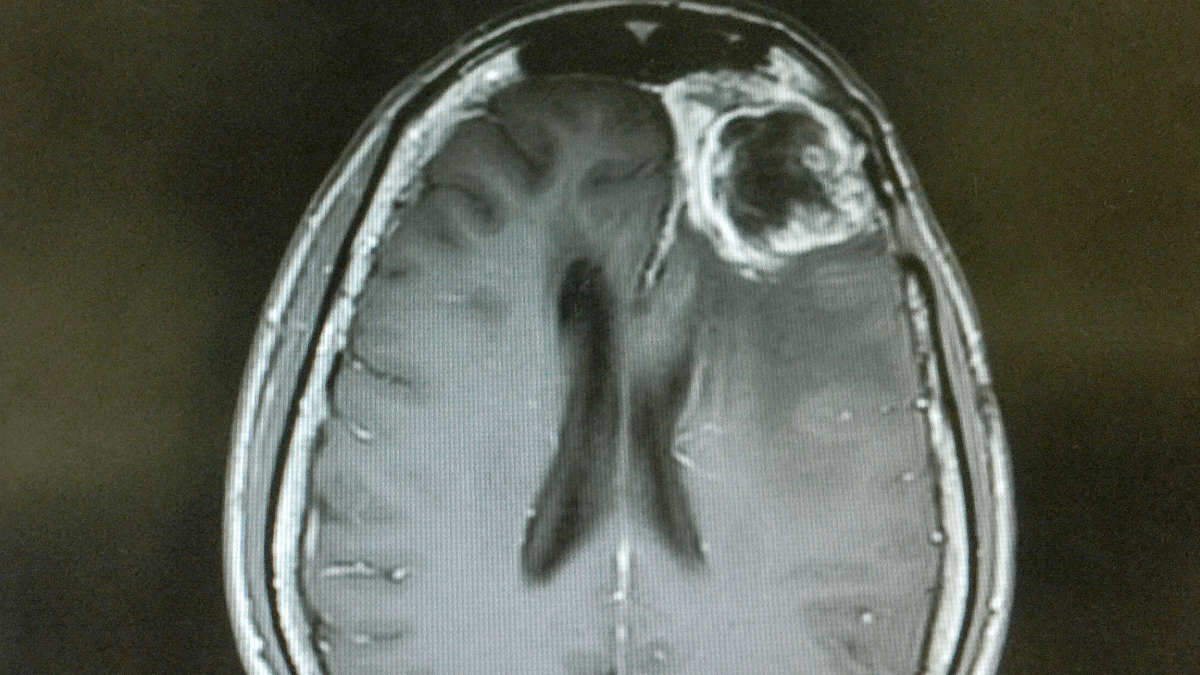

la vacuna SurVaxM se muestra prometedora para retrasar el regreso del glioblastoma

John Wishman fue diagnosticado con la forma más mortal de cáncer cerebral, glioblastoma, en el otoño de 2020. Dos años y medio después, todavía viaja y disfruta de la vida, una rareza para un cáncer con un tiempo de supervivencia promedio de solo 12 a 18 meses. Wishman, de 61 años, de Buffalo, Nueva York,…